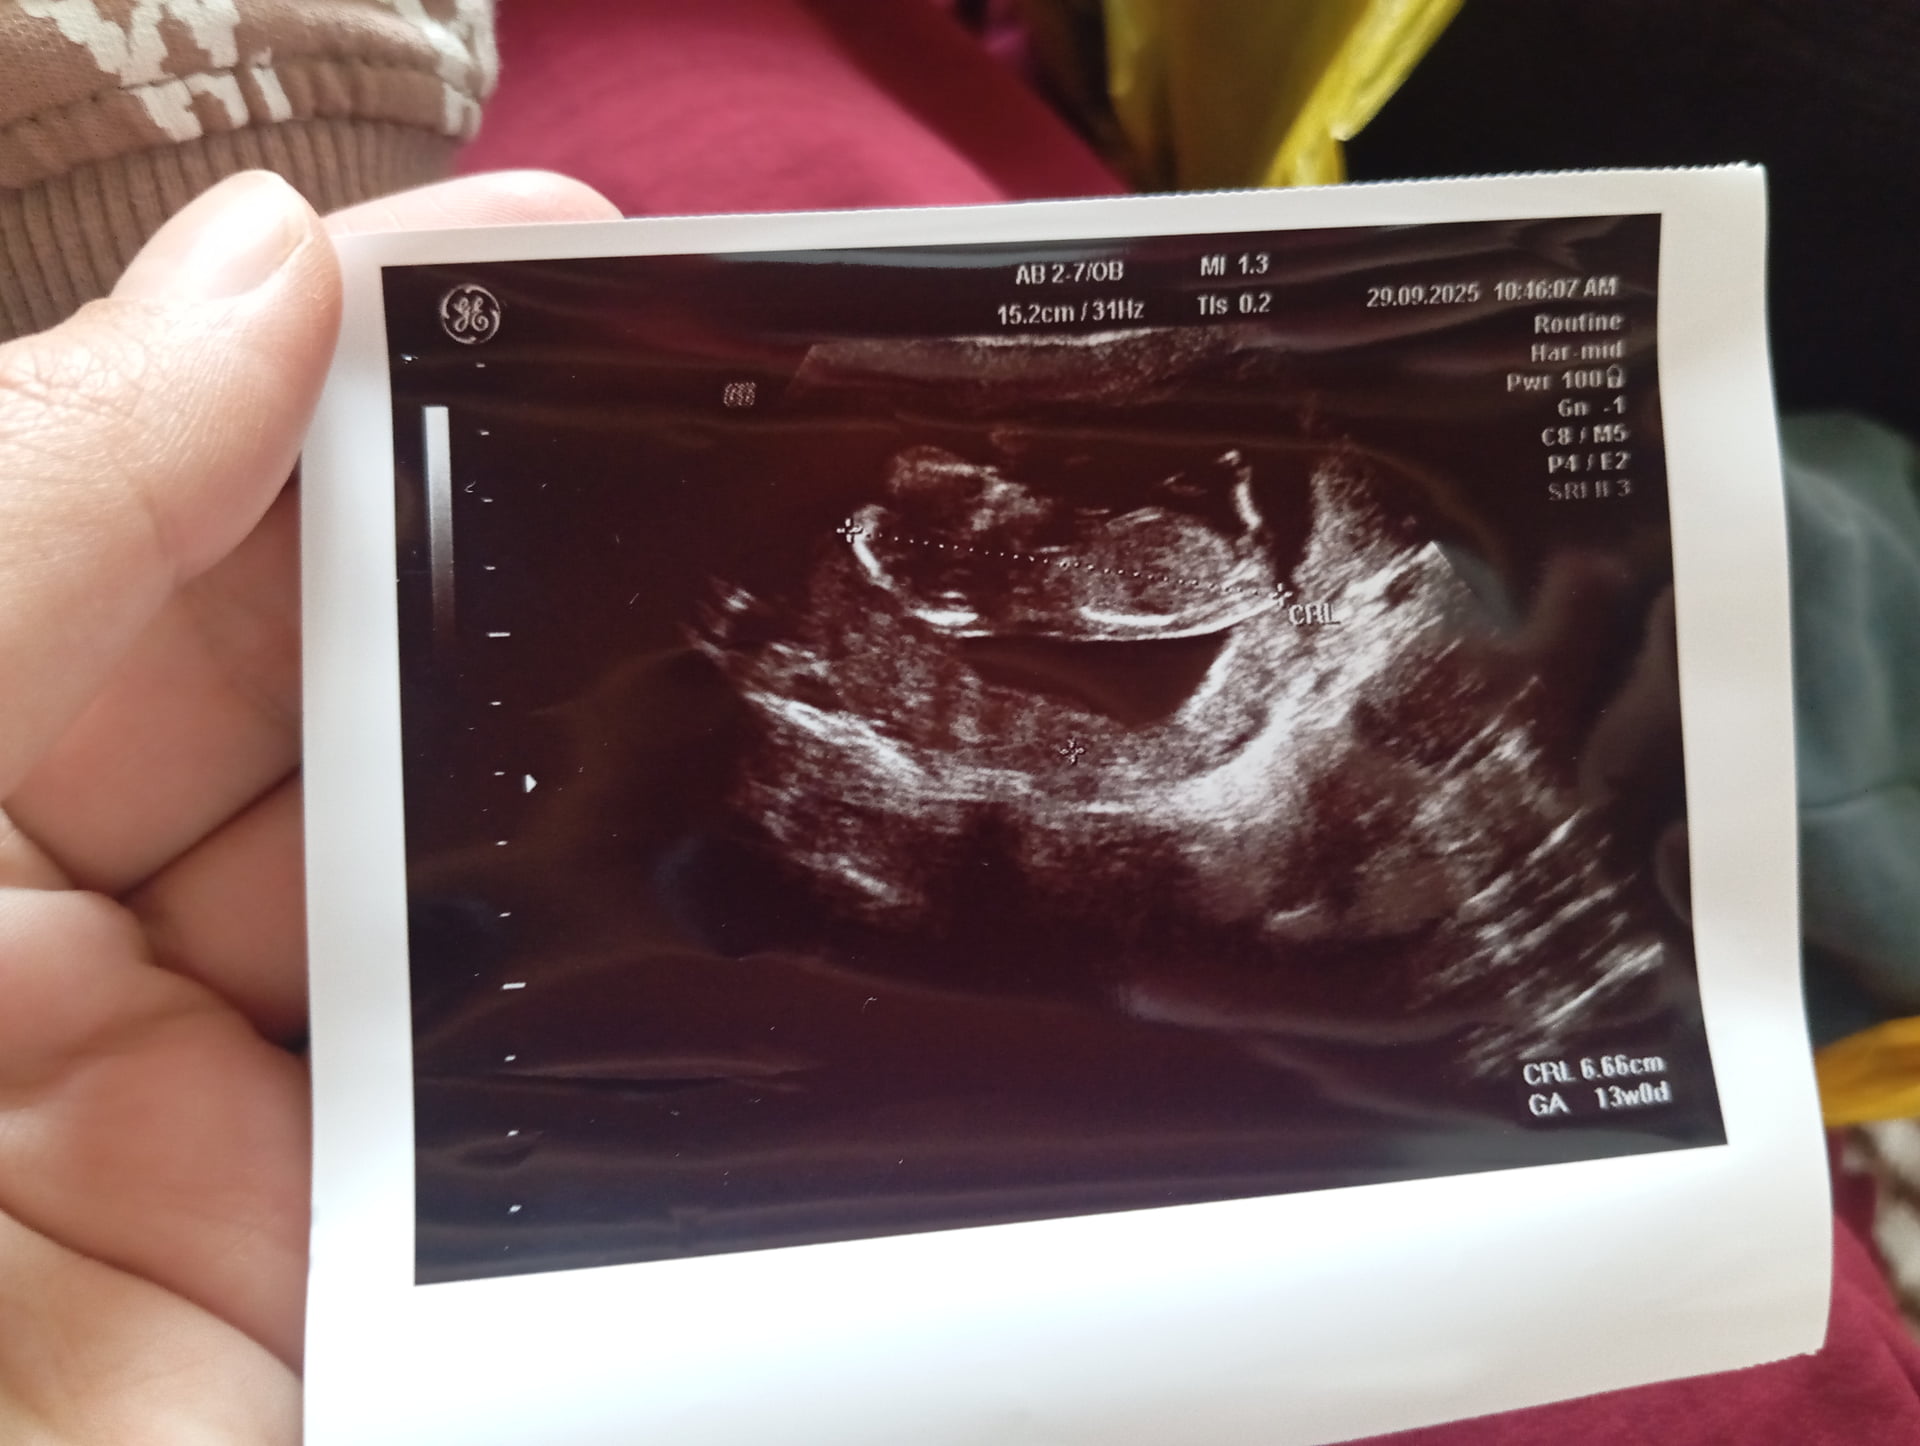

Bana da bakar mısınız

Kız gibii ![]()